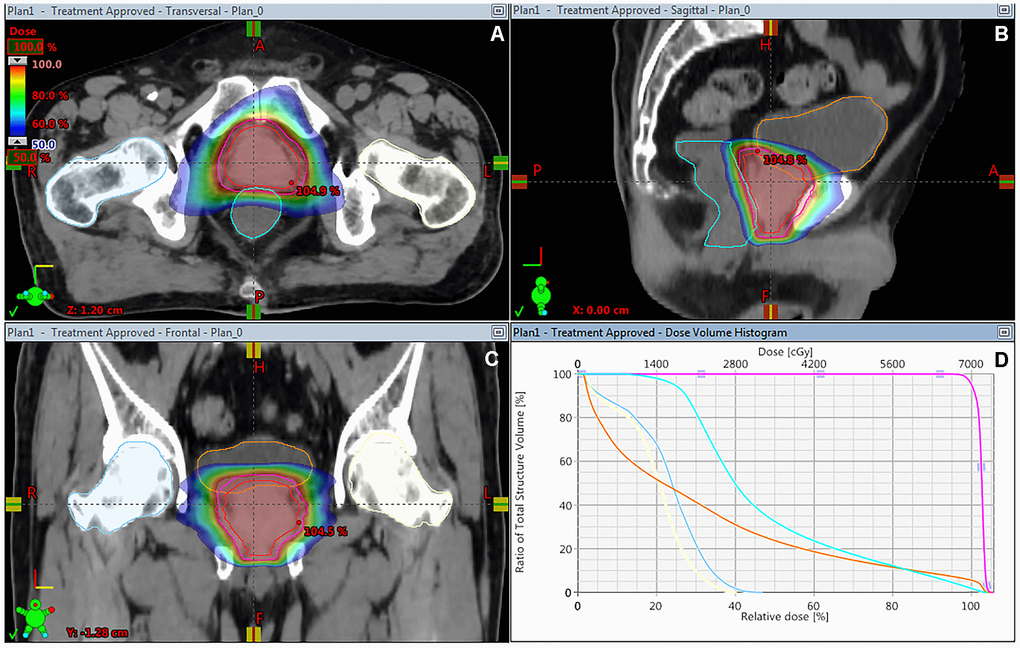

A total of 92 patients were enrolled between January 2016 and November 2018 and randomly assigned to either hypofractionated IG-VMAT (HFRT, 70 Gy/2.5 Gy/28 fractions; n = 46) or conventionally fractionated IG-VMAT (CFRT, 80 Gy/2 Gy/40 fractions; n = 46). All patients completed radiotherapy without interruption. Table 1 summarizes the clinical characteristics of patients in the two treatment arms. The median pre-therapy PSA level was 13 ng/mL. The dose coverage of PTV was not significantly different between the two groups (P = 0.639). Figure 1 shows a typical treatment planning of dose distribution and dose–volume histogram (DVH) with hypofractionated VMAT.

Figure 1. Dose distribution on the transverse (A), sagittal (B) and coronal (C) CT imaging, and DVH (D) of treatment planning of hypofractionated VMAT for patients with prostate cancer. DVH, dose–volume histogram; VMAT, volumetric modulated arc radiotherapy.